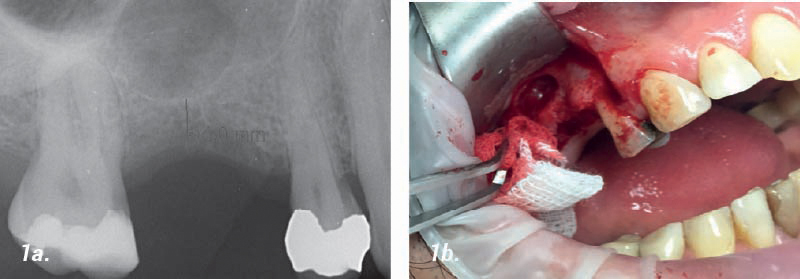

Elevación del seno sinusal

Caso presentado por el Dr. H. Jambrec, Ginebra, Suiza:

• 1a. Preoperatorio: La radiografía muestra una altura del hueso de 4 mm, qué no es suficiente para la colocación de un implante.

• 1b. Cirugía: Después de la preparación del colgajo se realizó el acceso sinusal mediante una pequeña fenestración (Tamaño aprox. 8mm).